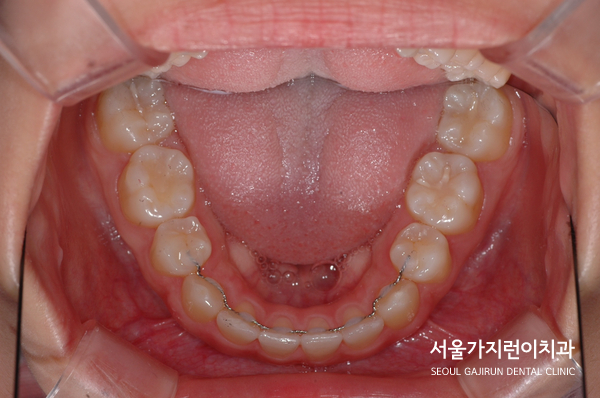

치료가 진행 되고 있을 때 찍은 사진인데요. 환자분의 경우 상악 치아가 하악 치아를 약간 덮고 있는 정상적인 교합으로 돨온 것을 확인할 수 있었습니다. 비뚤어진 치열도 말끔하게 배열되었는데요. 이와 동시에 무턱 증상도 많이 개선되어 교정이 끝난 후 4년 6개월간 안정적으로 유지된 것을 볼 수 있었습니다.